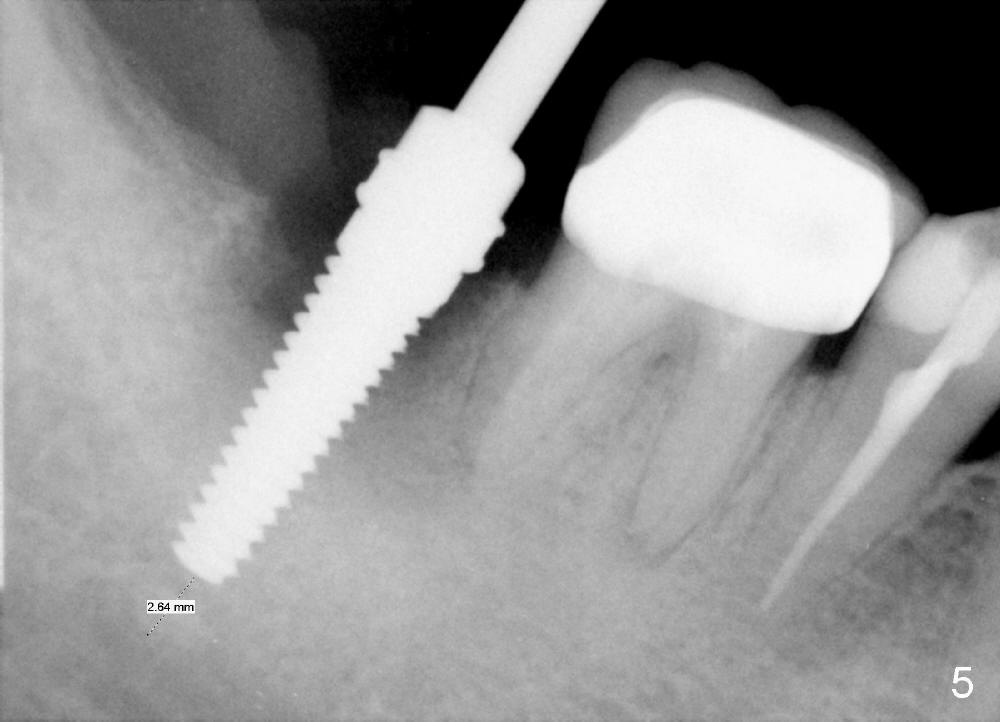

A 51-year-old man has experienced pain and swelling in the lower right 2nd molar for 7 months (Fig.1, P: post in the mesial root; <: gutta percha inserted into a buccal fistula). Fig.2 is taken immediately before extraction (<: purulent discharge from the mesiobuccal fistula) and immediate implant (Fig.3 implant design: 7x14 mm). A vertical root fracture is noted in the mesial root (Fig.4: lingual view). The septum is in fact absent, as compared to Fig.1. The mesiobuccal plate is low; the osteotomy starts lingual to the center of the socket. Fig.5 shows a 4.5x17 mm tap in place: approximately 3.5 mm in the new bone (~2.5 mm from the inferior alveolar canal). When a 7x17 mm tap (14 mm from the gingival margin) is placed in the socket, it looks relatively small. Fig.6 shows a 8x14 mm implant in place with a small gap distally. Mineralized cancellous allograft and Osteogen mixture is placed mainly buccally, followed by a thin strip of collagen dressing and sutures (Fig.7); an abutment (A) is placed to keep perio dressing in place. The perio dressing does not stay long. The buccal portion dislodges by itself 5 days postop. The lingual portion is removed in clinic. New dressing is going to be re-applied, because the buccal wound has not completely healed (Fig.8 <, albeit asymptomatic) with partial exposure of the bone graft (*). Why is the dressing lost so early? The abutment is not long enough; there is plenty of occlusal clearance (Fig.9 arrows). A longer abutment is used to increase mechanical retention for perio dressing (Fig.10). By the time the second perio dressing dislodges, the wound has healed (Fig.11, 13 days postop).